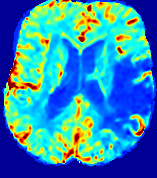

Slice #1Slice #2Slice #3Slice #4Slice #5Slice #6Dgtsuperscript𝐷gtD^{\text{gt}}Refer to captionRefer to captionRefer to captionRefer to captionRefer to captionRefer to caption(a)Refer to captionRefer to captionRefer to captionRefer to captionRefer to captionRefer to caption(b)Refer to captionRefer to captionRefer to captionRefer to captionRefer to captionRefer to caption(c)Refer to captionRefer to captionRefer to captionRefer to captionRefer to captionRefer to caption(d)Refer to captionRefer to captionRefer to captionRefer to captionRefer to captionRefer to caption(e)Refer to captionRefer to captionRefer to captionRefer to captionRefer to captionRefer to caption(f)Refer to captionRefer to captionRefer to captionRefer to captionRefer to captionRefer to captionRefer to caption000.060.060.060.120.120.120.180.180.180.240.240.240.300.300.30(mm2/s)𝑚superscript𝑚2𝑠(mm^{2}/s)

Figure 13: PIANO effectiveness and robustness testing: diffusion imaging via diffusion. Top row shows Dgtsuperscript𝐷gtD^{\text{gt}} used for simulating the ground truth pure diffusion. (a)-(f) refer to the results for D𝐷D estimated from the ground truth pure diffusion image time-series where Rician noise at levels 0%, 2%, 4%, 6%, 8%, 10% was added respectively.

Similarly, starting from the same initial condition C0superscript𝐶0C^{0} as in the ‘Advection Imaging’ experiment for each patient, we simulate concentration time-series {Cti(Ω)|i=0, 1,, 40}conditional-setsuperscript𝐶subscript𝑡𝑖Ω𝑖0140\{C^{t_{i}}\in\mathbb{R}(\Omega)|i=0,\,1,\,\ldots,\,40\} via a diffusion PDE, where we define the ground truth diffusivity D:=Dgtassign𝐷superscript𝐷gtD:=D^{\text{gt}} via the ADC map of the ISLES 2017 training set (ADC values are scaled by 0.000010.000010.00001 to ensure numerical stability):

Note this is likely not a spatially representative ground-truth for perfusion imaging, as it measures different effects from diffusion imaging. However, we still use it as a quasi-realistic pattern of diffusivity in the brain. We also added 2%, 4%, 6%, 8%, 10% levels of Rician noise to obtain simulations of ‘Diffusion Imaging’. The estimated Destsuperscript𝐷estD^{\text{est}} given concentrations of all noise levels for one patient are shown in Fig. 13, PIANO estimation results for all patients are summarized in Fig. 11 (b). Again, PIANO demonstrates its capability to recover the underlying diffusion field. In Fig. 13, when the noise level is increasing, some noisy patterns indeed appear in the associated Destsuperscript𝐷estD^{\text{est}}. Note that the ground truth diffusivity applied in this simulation experiment is about ten times larger than the diffusivity estimated in reality (Fig. 3, Fig. 4).